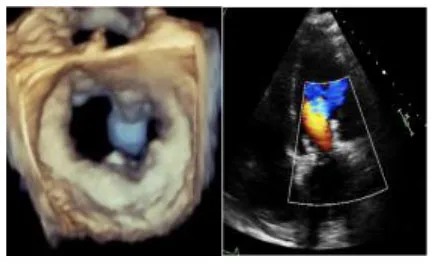

Figure 2

Three panels of figures (A–C) depicting the skirted Sapien 3 Ultra when crimped and loaded onto the transapical (shorter) delivery system. The prosthesis should be loaded upside down in relation to the aortic position.